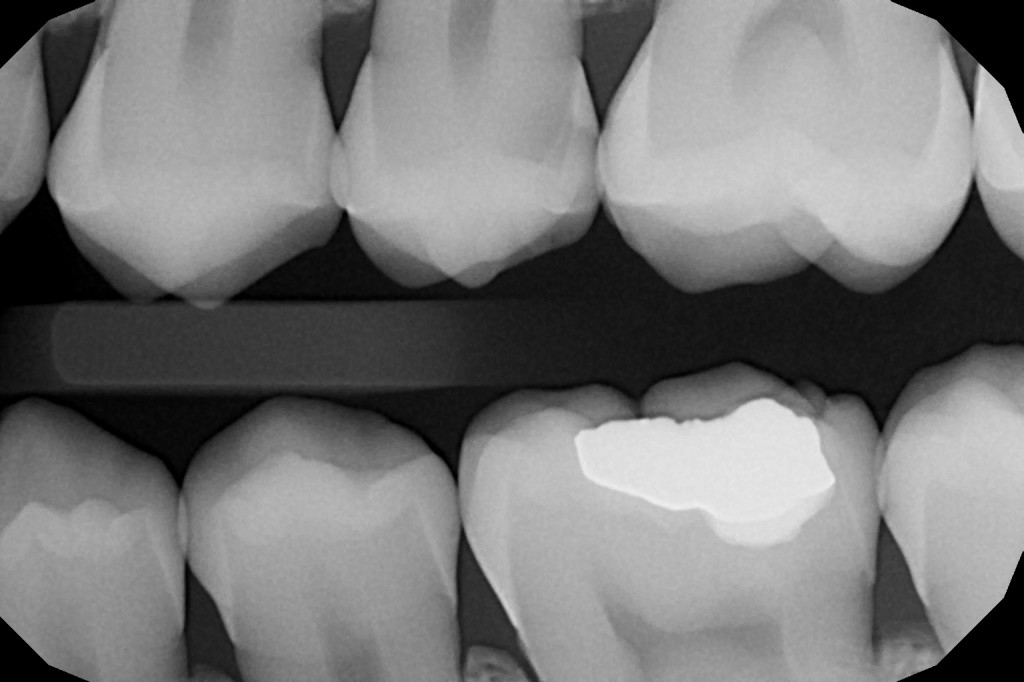

- Malé intraorální rentgenové snímky umožní detailní zobrazení zubů a včasné rozpoznání kazu.